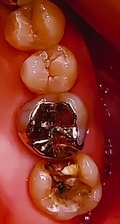

拝見したところ、左下の奥歯2本に古い**パラジウムインレー(銀の詰め物)**が装着されており、1本は外れていました。

パラジウムインレーは、経年劣化によって歯との境目が剥がれやすく、そこから虫歯が再発しやすいというデメリットがあります。

【Before】 銀歯の色が目立ち、周囲の歯との調和が取れていませんでした。

【After】 まるで天然の歯のような自然な白さと透明感を再現。患者様からは「見た目が自然で、他の歯とほぼ同じ色に仕上がったので、自信を持って笑顔を見せられるようになった」と大変ご満足いただけました。

| Before | 治療途中 | After | |